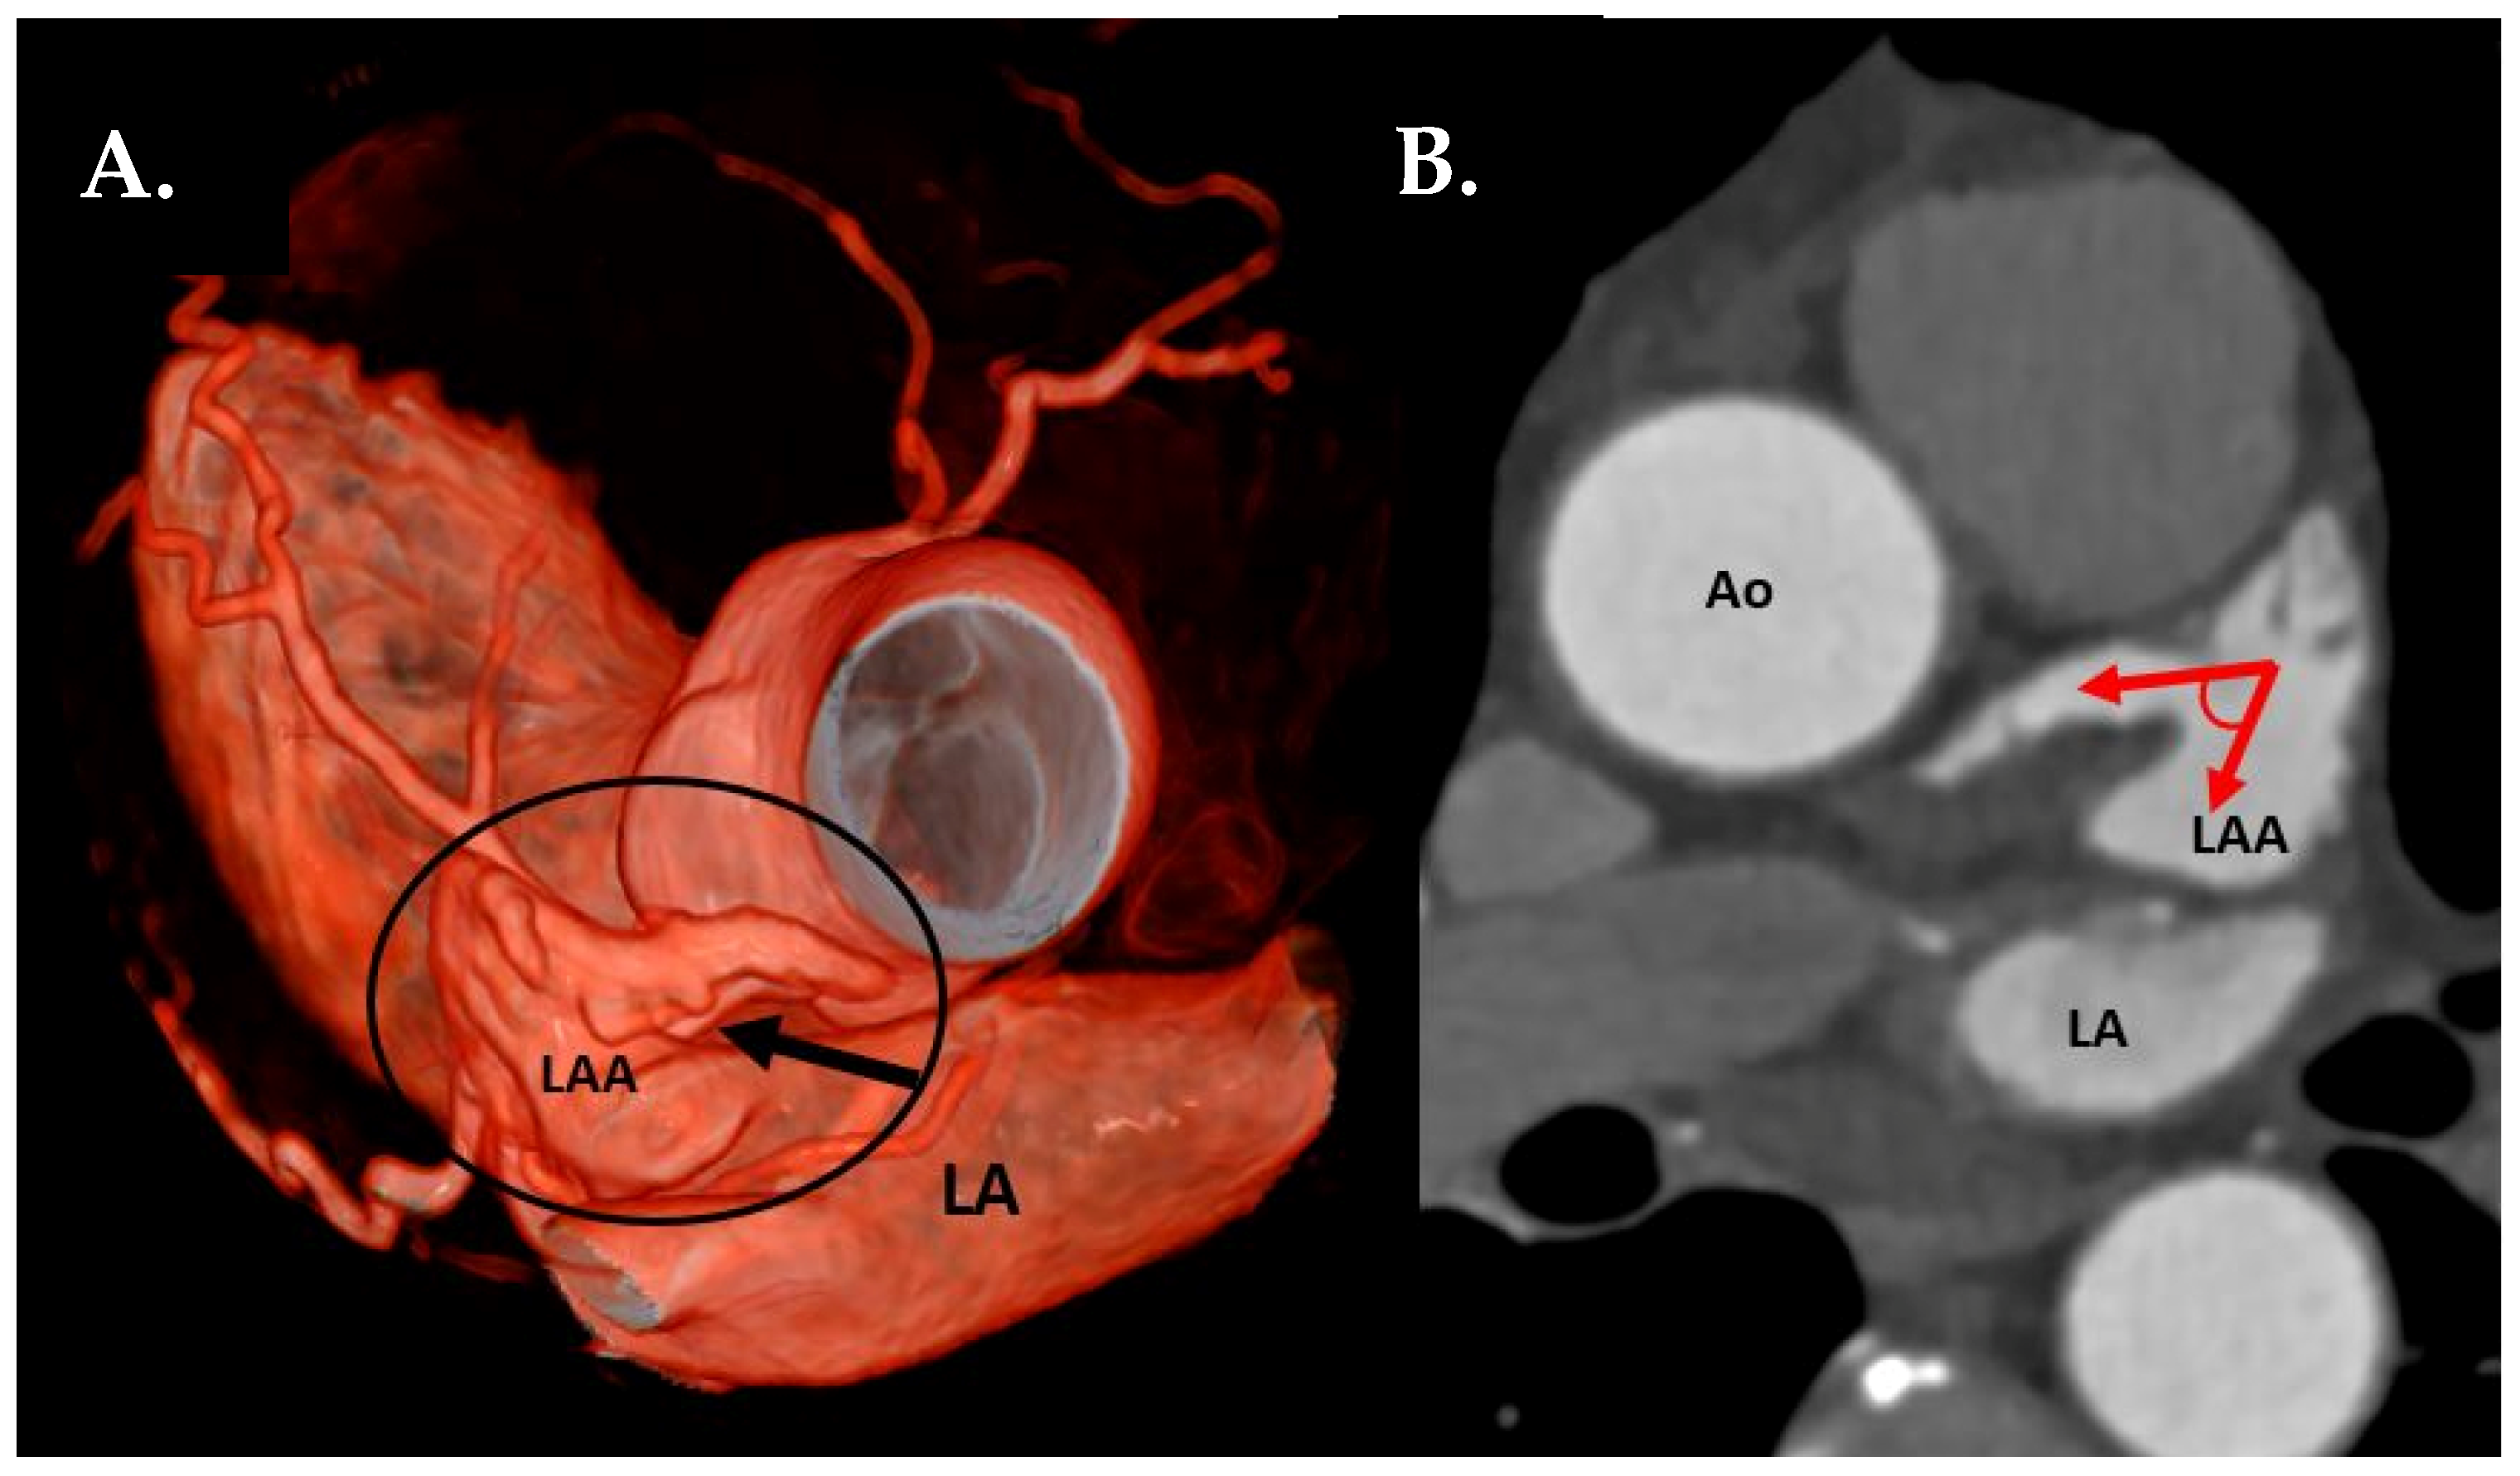

- LAA tip angulation was quantified using multiplanar reformation (MPR) and stratified as follows: ≤90° tip (Figure 2), 91–110°, >110°.

Figure 2. (A) CTA 3D-VRT reconstruction of LAA with a sharp tip angulation (≤90°) (black arrow). (B) sagittal plane with red arrows delineating sharp LAA tip angulation. Ao—aorta, LA—left atrium, LAA—left atrial appendage. - Left atrial anterior wall thickness (LAWT), also called LA ridge, was measured at three points antero-posteriorly (left—being the closest point to the LAA ostium, middle and right—the point of the LA anterior wall, which is most distant to the LAA) and the mean of the three points was calculated; LA ridge length was defined as the medio-lateral length of the LA ridge. These parameters were measured in axial plane at the left main (LM) coronary artery ostium and LAA ostium level using a digital caliper (Figure 3a).